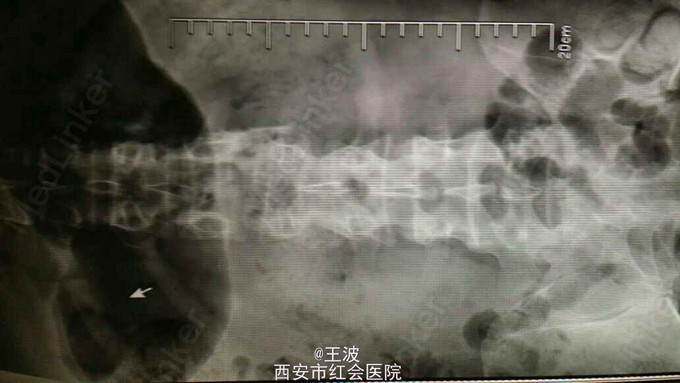

患者3年前外伤后腰1 2椎体爆裂骨折伴神经不全损伤,行胸12腰1椎板切除减压内固定,术后仍下肢麻木,左下肢无力,现拟取出内固定

查体:脊柱生理弯曲存在、无畸形、活动正常、局部皮下可触及金属内固定物、左侧足踝背伸减弱、肌力III级,膝以下平面感觉麻木、生理反射存在、右侧背伸减弱、肌力IV级.腰椎CT示腰椎骨折金属内固定术后状,未见明显脱位,椎间隙积气

患者神经损伤为陈旧性,已经不能完全恢复,即使术后取出内固定,下肢功能也不能恢复。术后X片显示:腰1椎体楔形改变、椎体内见高密度影、腰2椎体两侧不等高、腰1椎体缺如、椎间隙未见异常